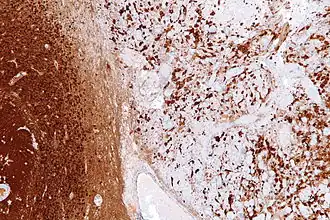

Gliosis is a nonspecific reactive change of glial cells in response to damage to the central nervous system (CNS). In most cases, gliosis involves the proliferation or hypertrophy of several different types of glial cells, including astrocytes, microglia, and oligodendrocytes. In its most extreme form, the proliferation associated with gliosis leads to the formation of a glial scar.

Reactive astrogliosis is the most common form of gliosis and involves the proliferation of astrocytes, a type of glial cell responsible for maintaining extracellular ion and neurotransmitter concentrations, modulating synapse function, and forming the blood–brain barrier.[3] Like other forms of gliosis, astrogliosis accompanies traumatic brain injury as well as many neuropathologies, ranging from amyotrophic lateral sclerosis to fatal familial insomnia. Although the mechanisms which lead to astrogliosis are not fully understood, neuronal injury is well understood to cause astrocyte proliferation, and astrogliosis has long been used as an index for neuronal damage.[4] Traditionally, astrogliosis has been defined as an increase in intermediate filaments and cellular hypertrophy as well as an increase in the proliferation of astrocytes. Although this hypertrophy and proliferation in their extreme form are most closely associated with the formation of a glial scar, astrogliosis is not an all-or-none process in which a glial scar forms. In fact, it is a spectrum of changes that occur based on the type and severity of central nervous system (CNS) injury or disease triggering the event.[5] Changes in astrocyte function or morphology which occur during astrogliosis may range from minor hypertrophy to major hypertrophy, domain overlap, and ultimately, glial scar formation.[5] The severity of astrogliosis is classically determined by the level of expression of glial fibrillary acidic protein (GFAP) and vimentin, both of which are upregulated with the proliferation of active astrocytes.[4][6]